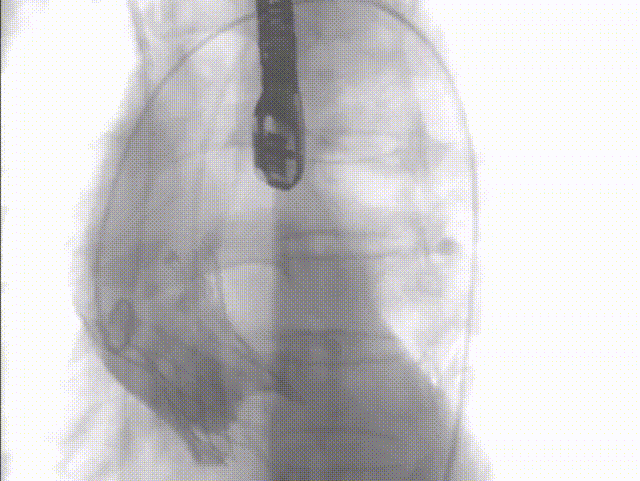

手术过程概览

整体入路造影,右侧细,走左侧为主入路,左侧用外周球囊预扩后送大鞘

术前压差163mmHg

20mm球囊预扩,球囊下滑

再次预扩,球囊上跳

瓣下3mm定位

释放到工作位,瓣下5mm左右

缓慢脱钩

左冠窦侧微量反流

22mm球囊后扩

患者压差从163mmHg降为6mmHg,效果显著。